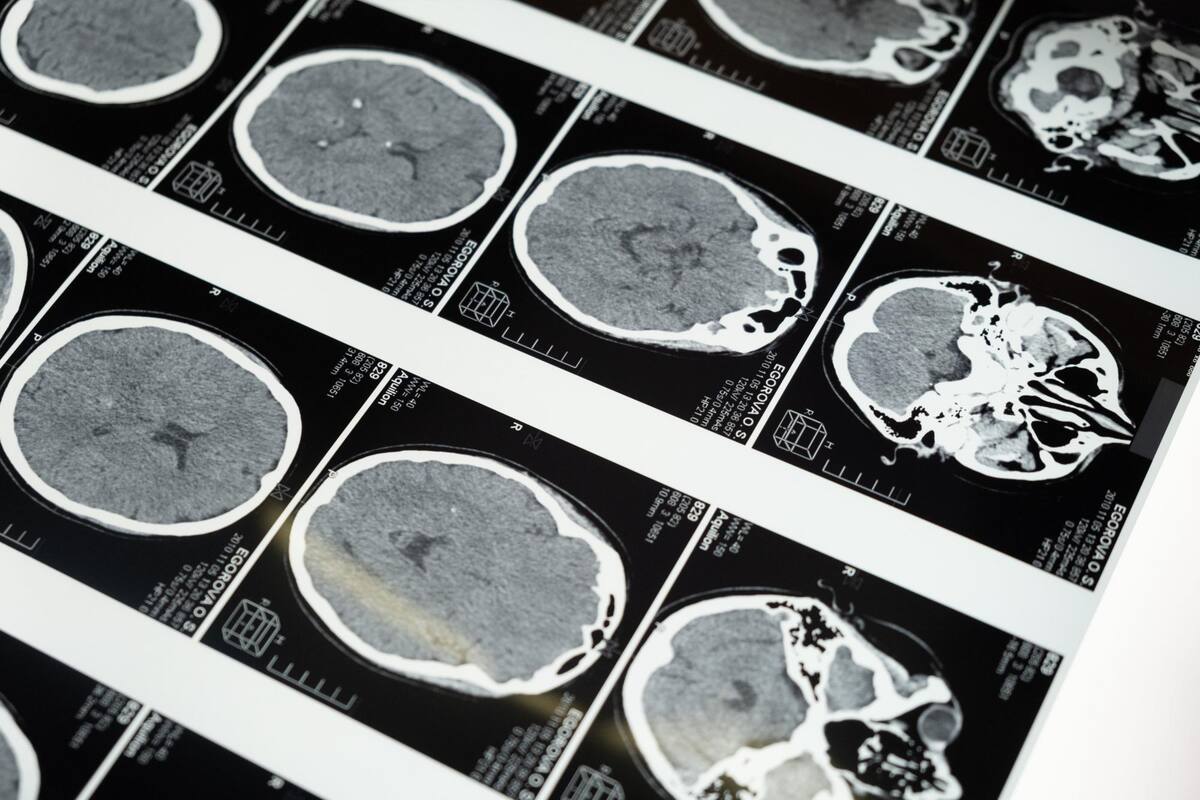

En el intrincado tejido del sistema nervioso, las enfermedades neurodegenerativas se alzan como sombras implacables que afectan a millones en todo el mundo.

Desde Alzheimer hasta Parkinson, estas condiciones debilitan progresivamente las funciones cerebrales, desafiando no solo a los afectados sino también a la comunidad médica y científica.

En el corazón de la complejidad del sistema nervioso, las enfermedades neurodegenerativas se manifiestan como un conjunto de trastornos que afectan las células nerviosas, conocidas como neuronas.

Estos trastornos, como el Alzheimer, Parkinson, ELA (esclerosis lateral amiotrófica) y la enfermedad de Huntington, comparten una característica común: la degeneración progresiva de las neuronas, lo que conduce a la pérdida gradual de funciones cerebrales vitales.